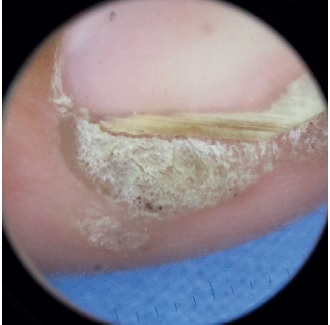

A primeira descrição de bleomicina intralesional para o tratamento de verruga viral ocorreu na década de 1970, e desde então diversos estudos evidenciaram suas eficácia e segurança. Para muitos autores essa é uma excelente opção terapêutica para lesões em topografias de difícil abordagem, em especial a região periungueal (Figuras 2 e 3), e para lesões recalcitrantes, mesmo em imunossuprimidos.3,8,9,11,13,14,16,17

Na primeira semana após o procedimento, para lesões localizadas nas mãos e/ou nos pés, espera-se que ocorra a formação de crostas hemáticas e enegrecidas. Isso se deve à diminuição absoluta do fluxo sanguíneo, que resulta em necrose e posterior desaparecimento da lesão (Figura 4). Em geral, ocorre resolução no prazo de duas a quatro semanas. Nas verrugas faciais ocorrem a regressão gradual e o desaparecimento da lesão sem a formação de crosta.3,11 Provavelmente o fluxo sanguíneo diminui após injeção, porém não é completamente interrompido, devido à rica vascularização dessa topografia. A indução de apoptose endotelial e o dano direto ou indireto no queratinócito podem resultar em regressão da verruga sem necrose ou escara.11